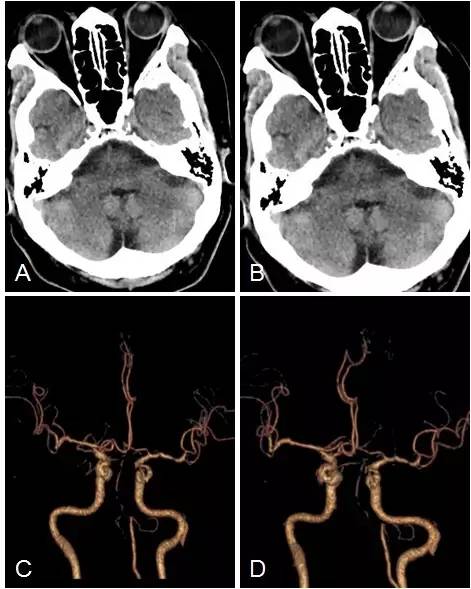

术后立即复查头CT未见出血(图6A,B)。

术后颅内动脉CTA:双椎动脉V4段闭塞;与术前CTA相比,右椎动脉V3闭塞段长度有增加(图6C,D)。

图6